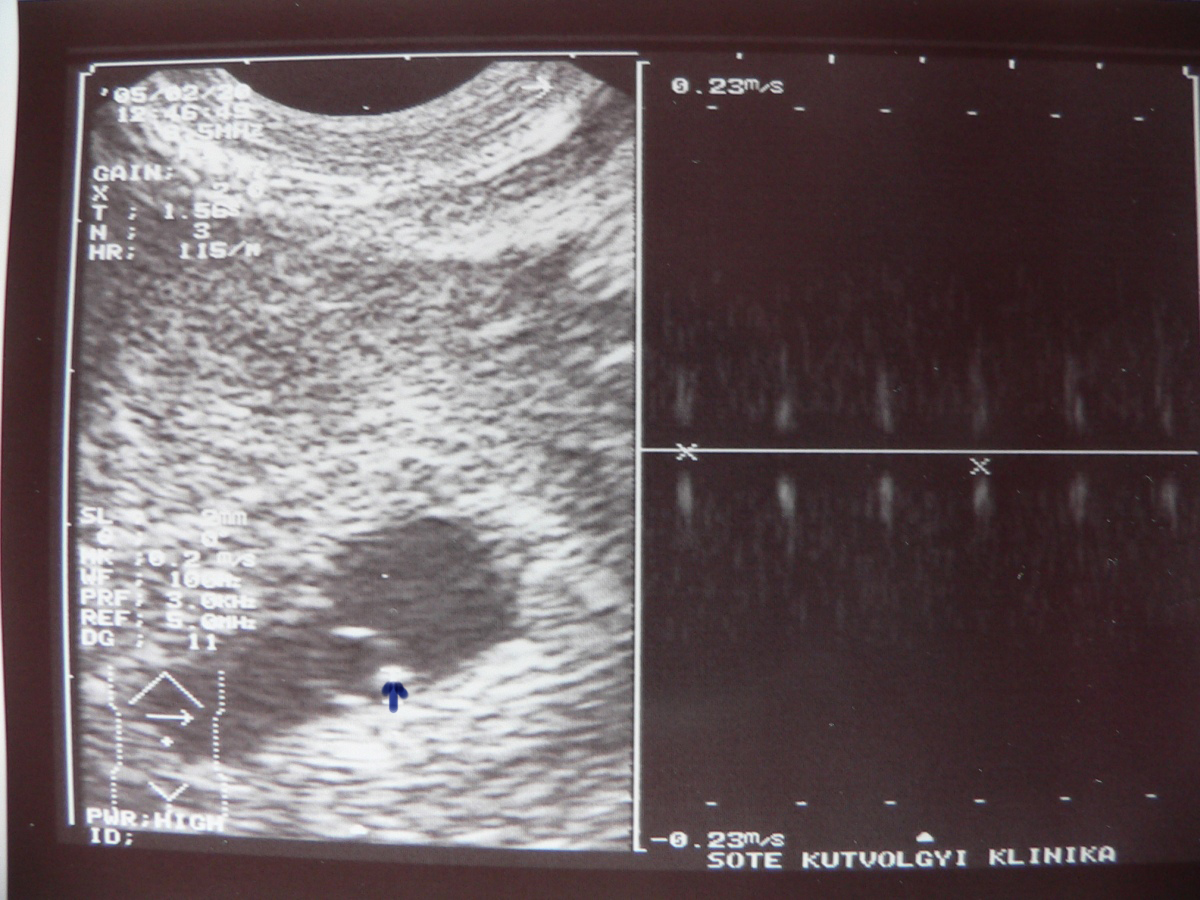

| 5 hetes, 4.5 mm. A kis nyilacska szerűség mutatja a szívét. Mellette a függőleges vonalak a szívverését mutatják.. :-) | |